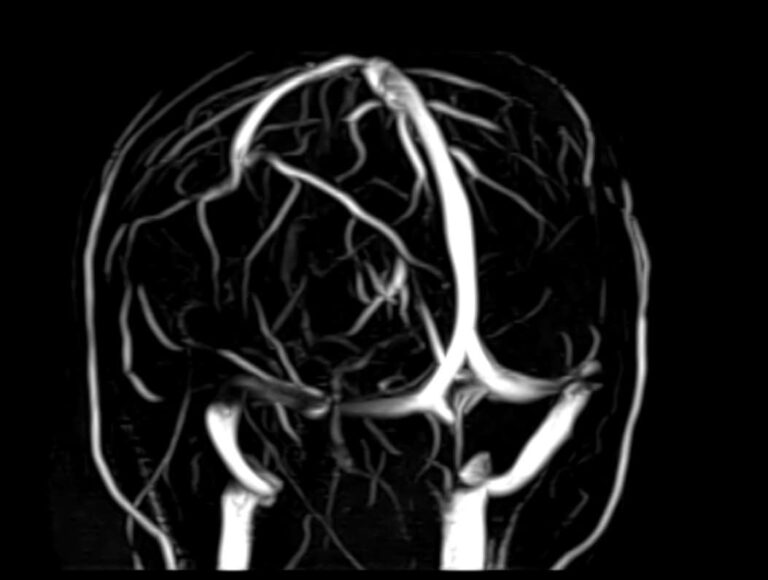

Назад МР-венография головного мозга в СПБ

Магнитно-резонансная венография головного мозга позволяет детально изучить особенности анатомического и функциональной состояния венозного русла головы и шеи. С помощью данного исследования можно исключить многие серьезные заболевания сосудов головного мозга и начать своевременное лечение.